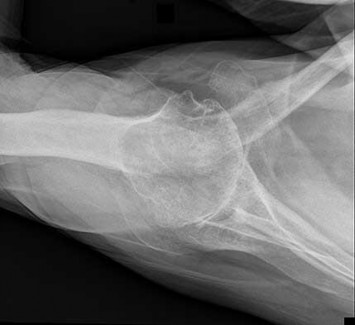

Question 4:

A 12-year-old obese male presents with left thigh pain and an antalgic gait for 4 weeks. He has been entirely unable to bear weight on the left leg for the past 2 days. Radiographs show a slipped capital femoral epiphysis (SCFE) with a slip angle of 60 degrees. What is the most significant risk factor for the development of avascular necrosis (AVN) in this patient?

Correct Answer: Inability to bear weight

Explanation:

The clinical inability to bear weight, even with crutches, defines an unstable SCFE according to the Loder classification. Unstable SCFE carries a significantly higher risk of avascular necrosis (AVN), historically up to 50%, compared to stable SCFE where AVN is rare. While a severe slip angle increases the technical difficulty of fixation, stability is the primary predictor of AVN.